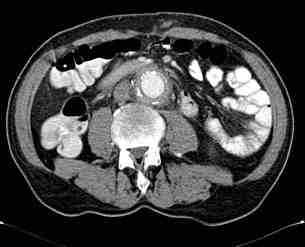

Figura 1: Se destaca la presencia de colección de 8×7 cms, con gas en su interior.

Figura 2: Se Observa una disminución significativa y la práctica desaparición del absceso quedando únicamente alteración de la grasa circundante